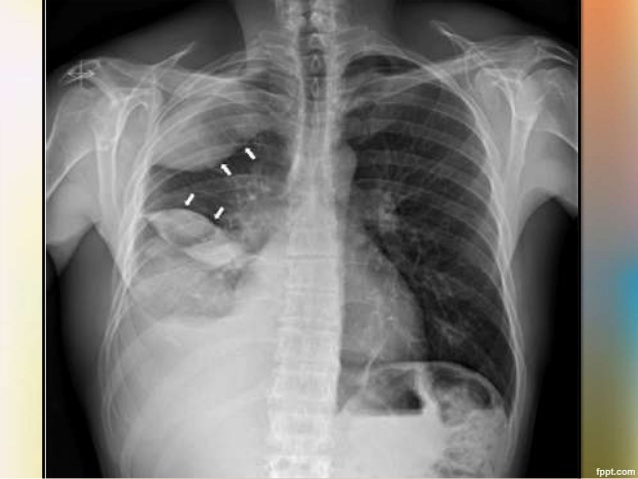

- X-rays and CT scans. Both methods of examination will be performed on the chest to indicate the presence or absence of fluid in the pleural space.